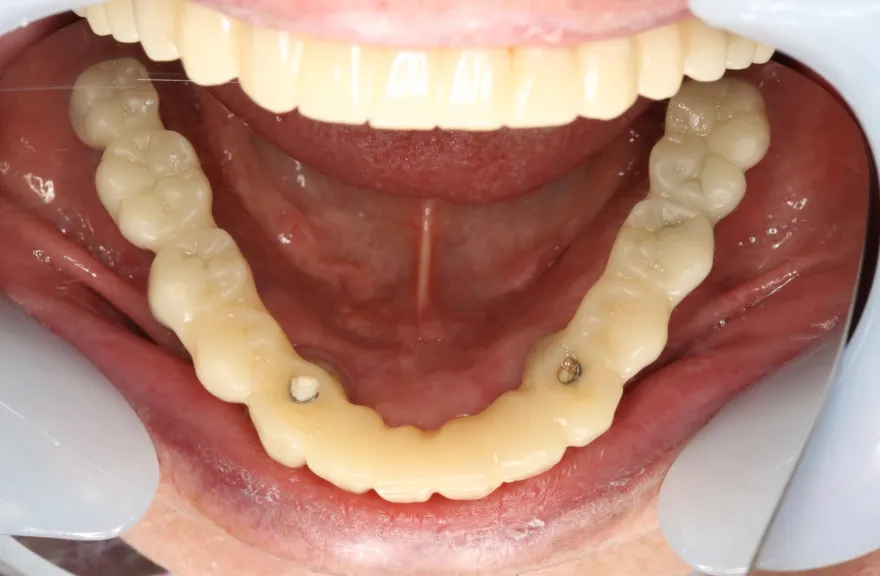

骨格の前後的な差がある方でした。術前のレントゲンより、上下で歯牙の損傷に明らかな差があるのがみてとれます。

上の歯がないところにインプラント治療を行い、上顎は全てインプラントフィクスチャーによる固定性の歯を入れられることも費用的には可能な方でした。

今回の症例では、敢えて上顎は総義歯形態をとり、骨格的な前後の差を解消するよう工夫しました。

上顎の残っていた歯も、差し歯としては使えずとも、敢えて根だけ残すことによって組織を温存し、義歯の安定に寄与するよう設計しました。

ここまで全体的にしっかり治療しておけば、今後の人生においてトラブルになるようなことにはならないでしょう。 - 治療のリスク

上顎の総義歯は、馬蹄形という上顎の覆う部分が小さいタイプで作成いたしました。強度に劣るため、割れる可能性があります。

下顎のクラウン・ブリッジは、丁寧な形成・印象処置と自費専門の技工士によって製作されたもので、虫歯による損傷が今後起こりにくいとは考えますが、定期的なメンテナンスは必須であり、生涯もつものではありません。

神経のない歯(失活歯)は神経がある歯に比べて力が大きくかかりやすく、根が割れたりするリスクがあります。割れ方にもよりますが、基本的には歯が割れてしまうと抜歯処置を行わなければならないことがほとんどです。